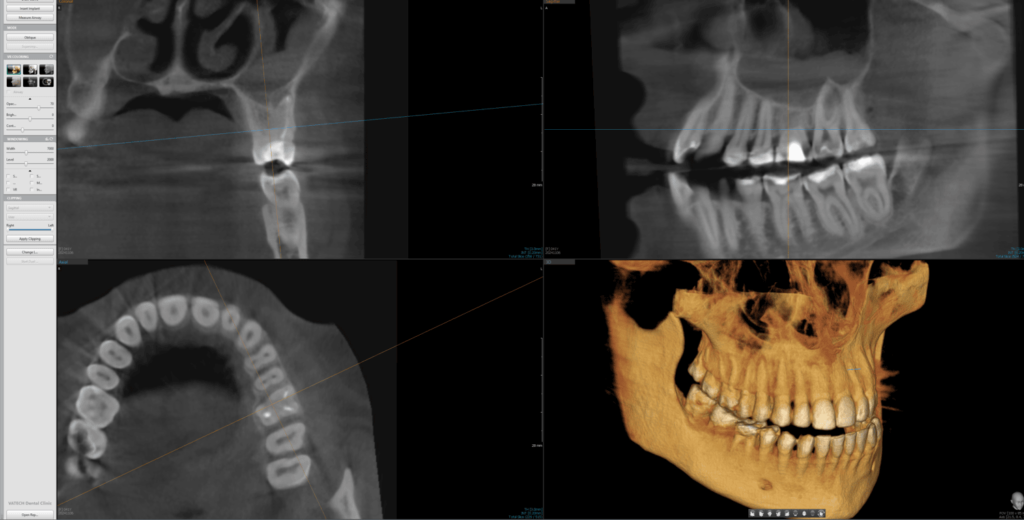

3D/CBCT (kompjuterizovana tomografija sa konusnim snopom) je napredni postupak snimanja u stomatološkoj radiologiji. Koristeći tehnologiju sličnu onoj kod standardnih medicinskih skenera, ali sa drastično smanjenom količinom zračenja, ova metoda pruža izuzetno precizne slike dentalnih struktura. 3D/CBCT omogućava pravljenje detaljnih trodimenzionalnih snimaka koji daju stomatologu potpuni uvid u zubne i koštane strukture, bez skrivenih ili iskrivljenih delova.

2D snimci su uobičajena vrsta snimanja koja prikazuje zube i vilice u jednoj ravni. To uključuje snimke pojedinačnih zuba, ortopane i slično. Za razliku od tradicionalnih 2D snimaka, 3D snimci zadržavaju pravilan odnos struktura, predstavljajući visinu, dužinu i širinu svih struktura u pravom odnosu 1:1.

Ova vrsta snimanja je posebno korisna za kompleksnije dentalne procedure, kao što su oralno-hirurške intervencije, postavljanje dentalnih implanata, ili tretman zuba sa višestrukim korenovima. Zahvaljujući 3D/CBCT snimcima, stomatolozi mogu precizno planirati i sprovoditi ove intervencije.